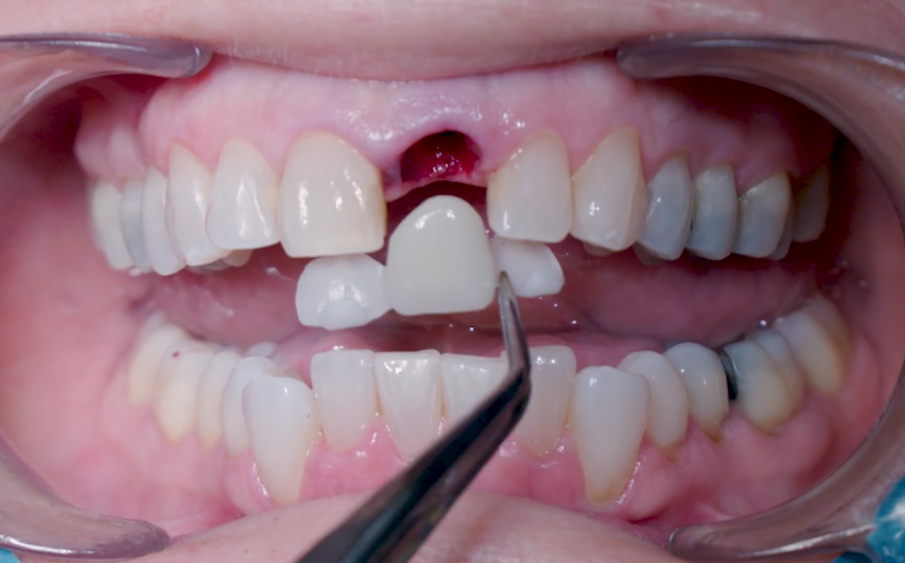

Un abutment provvisorio di Ø 4 mm con un’altezza gengivale di 2,5 mm è stato posizionato sull’impianto e non ha mostrato interferenze sulla cresta ossea, consentendo un adeguato profilo di emergenza (Fig. 19). Il guscio del dente, che è stato progettato e fresato in PMMA prima della procedura (Figg. 20, 21), è stato testato per assicurarsi che i contorni e le ali di ritenzione fossero adeguati e non causassero interferenze (Figg. 22, 23). Il lato palatale, comprendente una piccola porzione del bordo incisale, è stato aperto per consentire l’accesso al canale della vite (Figg. 24, 25). Le ali laterali del guscio del dente permettono alla corona provvisoria di rimanere immobile durante la procedura di prelievo, problema comune che i medici si trovano ad affrontare quando eseguono la tecnica pick-up immediata. Il guscio del dente è stato incollato al moncone provvisorio con composito flow fotopolimerizzabile ed è stato lasciato un sottile profilo di emergenza sulla porzione sottogengivale con lo stesso materiale (Fig. 26). A questo punto, le ali di ritenzione sono state rimosse. Senza compressione sui tessuti molli, la corona provvisoria è stata posizionata e il bordo incisale è stato ritoccato per garantire che il dente antagonista non lo toccasse nei movimenti di escursione. La corona provvisoria è stata cementata con un torque di 25 Ncm e il foro di accesso della vite è stato chiuso e lucidato correttamente (Fig. 27). Il paziente è stato visitato sette giorni dopo per il controllo radiografico postoperatorio e periapicale (Figg. 28, 29).

Figg. 22, 23_Valutazione dell’adeguatezza del guscio provvisorio.